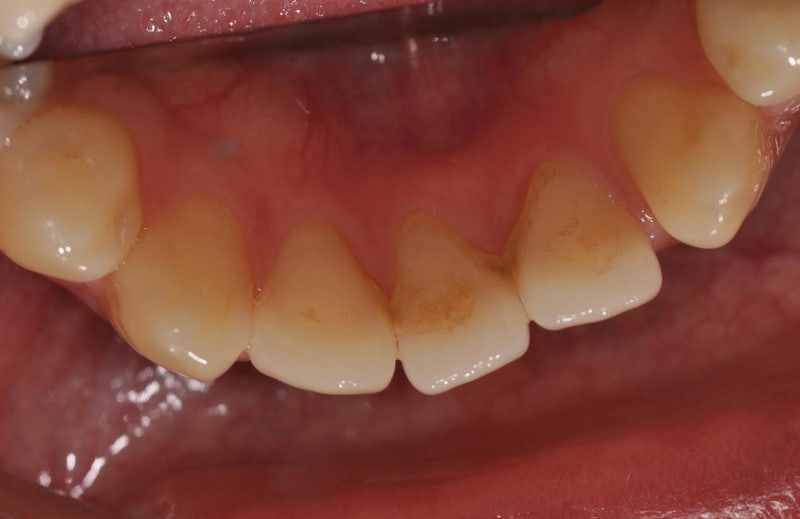

비숑모찌는 힐링힐스 동물치과병원을 방문해 스케일링과 치아검진을 받았습니다. 수술 준비를 하고 있는 모찌와 간호사님~ 마취 후 자세히 살펴보았습니다! 왼쪽 어금니 협측와에 구멍이 났고, 잇몸에 치은종양이 있었고, 오른쪽 어금니의 법랑질이 약간 깨졌으며, 아래 어금니 안쪽 설측와에는 치석이 가득했습니다. 수술 후 치아에 구멍이 난 사진과 강아지의 치은종 사진입니다. 완전히 치유되었습니다. 법랑질이 침식되면 치아의 손상이 더욱 악화되어 파절이 더욱 심해질 수 있으므로 사진과 같은 레진치료가 필요합니다. 아래어금니 안쪽의 설와에도 레진치료를 시행하였습니다. 광고 이후 계속됩니다. 다음 주제 작성자 취소 강아지 치은종/개 치아 구멍/개 수지 치료 – 애견 치과 재생 8 좋아요 0 좋아요 공유 0:00:00 재생 음소거 00:00 00:15 실시간 설정 전체 화면 해상도 자동 480p 자막 비활성화 재생 속도 1.0x(기본) 해상도 자동(480p) 1080p HD 720p HD 480p 270p 144p 자막 설정 비활성화 옵션 글꼴 크기 배경색 재생 속도 0.5x 1.0x(기본) 1.5x 2.0x 알 수 없는 오류가 발생했습니다. 도움말이 음소거되었습니다. 도움말 라이센스 이 영상은 고화질로 재생할 수 있습니다. 설정에서 해상도를 변경해보세요. 자세히보기 0:00:00 접기/펼치기강아지 치은종/강아지 구멍/강아지 레진 치료강아지 치은종/강아지 구멍/강아지 레진 치료 – 강아지 치과#강아지 레진 치료#강아지 치은종#강아지 치아#치아에 구멍 # DogDentistry #AnimalDentistry 치료를 마치고 병원 테라스에서 뛰어다니고 노는 모습이 뿌듯했고 기분도 좋아졌습니다. 오늘 치료는 잘 끝났습니다^^ 튼튼한 치아가 잘 유지되어 다음 정기 검진도 잘 받으실 수 있을 것 같습니다. 예쁜 치아를 직접 만나보시길 바랍니다 🙂 힐링힐스 동물치과의 인스타그램을 방문해 주세요 🙂 힐링힐스 동물치과병원은 인스타그램을 사용하고 있습니다. • 힐링힐스 동물치과병원 프로필은 게시물 607개, 팔로워 327명, 팔로우가 있습니다. Ying 189명, 게시물 607개 – 힐링힐스 동물치과병원 인스타그램 사진 및 동영상 보기(@healinghillsvet) www.instagram.com 반려동물의 치과 진료는 사람만큼 여러 번 치료를 받을 수 없기 때문에 더욱 완전하고 세밀해야 합니다. 소중한 강아지/고양이의 치아를 살리고 성공적인 치과치료를 제공하기 위해 힐링힐스는 휴먼치과 또는 휴먼치과대학병원에서 사용하는 최첨단, 고사양 치과장비를 갖추고 끊임없이 연구하고 노력하고 있습니다. 안전을 최우선으로 생각하여 최고의 결과를 만들어 갑니다. 힐링힐스 동물치과병원 50m NAVER 더보기 /OpenStreetMap 지도데이터 x 네이버(주) /OpenStreetMap Map Controller Legend Real Estate 부동산 면 동시 산오리읍 군, 구, 시, 도 힐링힐스 동물치과병원 9- 경기도 성남시 분당구 동판교로52번길 11 힐링힐스 동물치과병원 힐링힐스 동물치과병원 031-708-0078 경기도 성남시 동판교로 9-11 동판교로 52번- 분당구 분당길 진료시간 : 월~토요일 09:30~18:00 (일요일, 공휴일 휴무) 하루 1~2회 집중수술을 진행합니다! 모든 시술은 방문 전 예약 부탁드립니다 🙂